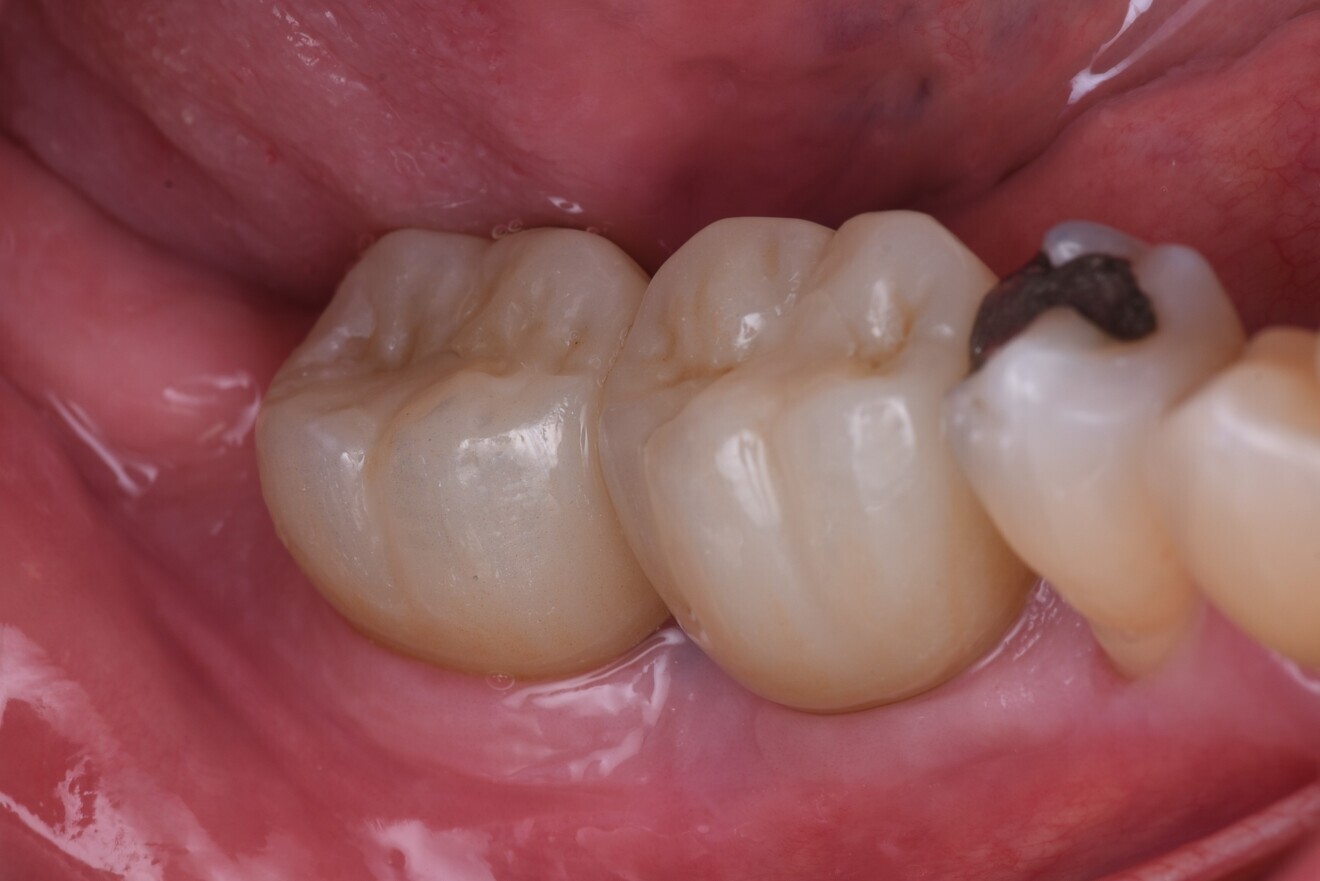

The immediate placement of the CONELOG PROGRESSIVE-LINE implants in both molar sockets proceeded smoothly, achieving excellent primary stability. The hard and soft tissue was well maintained, and excellent soft-tissue thickness and a stable band of keratinised tissue were achieved (Figs. 13–16). This approach not only preserved the existing bone and soft tissue but also provided a solid foundation for future prosthetic restoration. This case highlights the importance of case selection and choice of implant and grafting material in optimising long-term outcomes in implant dentistry.

Fig. 13: Healing abutments removed to reveal soft-tissue healing.